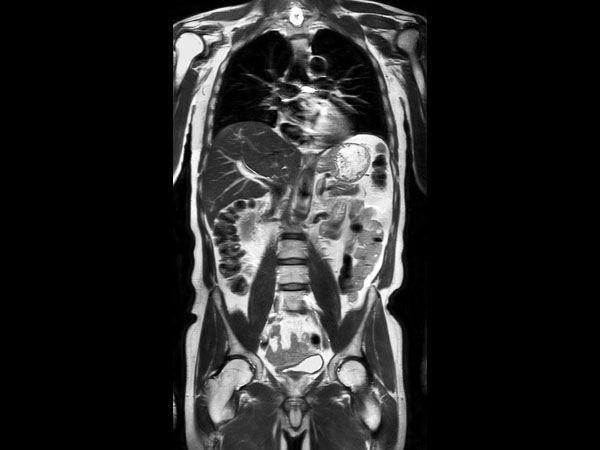

Coronal T2w TSE (MobiView)